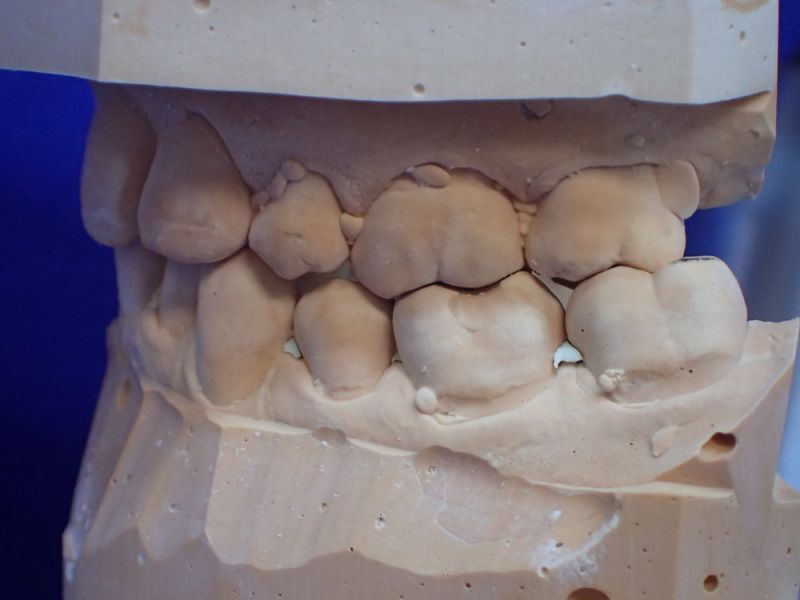

Patientin von der dänischen Grenze erhält einen adjustierten Aufbissbehelf